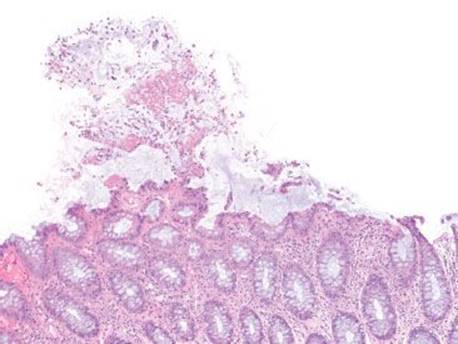

Figure 4.83 Pseudomembranous pattern, early. The eruptive pseudomembrane is hard to miss, even at low magnification. Interestingly, the background mucosa sometimes shows little to no change, as seen here.

Figure 4.84 Pseudomembranous pattern, marked. Severe cases of pseudomembranous colitis may require colectomy, as in this case. There is extensive tissue necrosis and only rare residual crypts (arrowheads) remain.